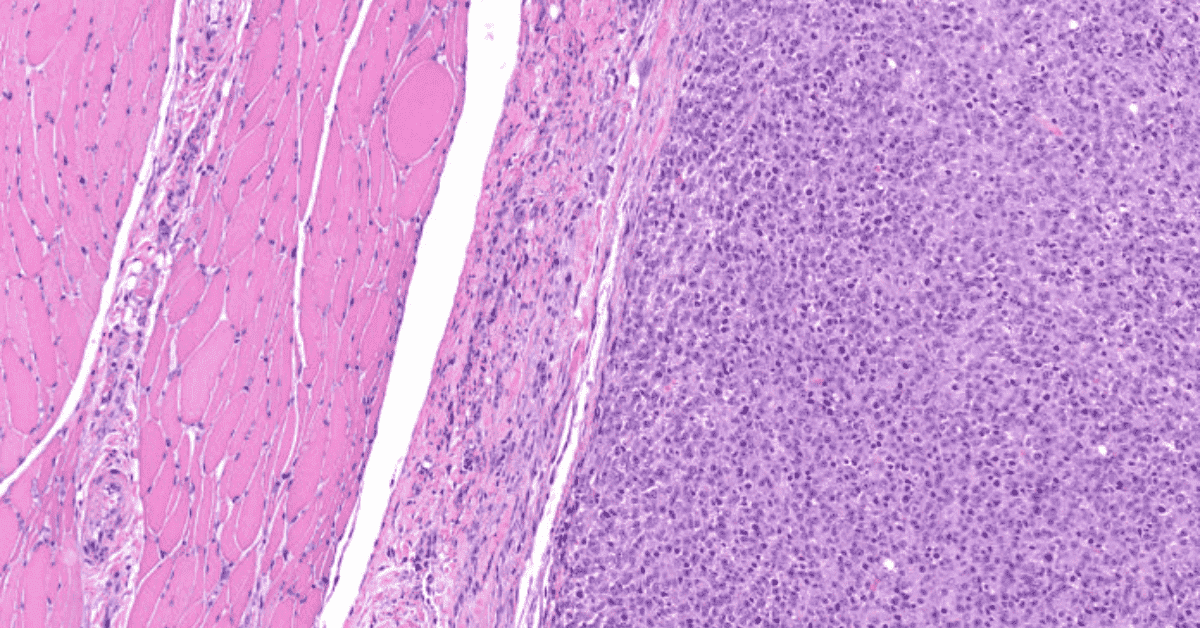

Soft Tissue Sarcoma - Pathology - Orthobullets

www.orthobullets.com

www.orthobullets.com

rhabdomyosarcoma pathology orthobullets sarcoma tissue soft bone cell 51c topic donnell patrick

Rhabdomyosarcoma: A Musculoskeletal Pathology Case Study | E-Gallery

www.unmc.edu

www.unmc.edu

rhabdomyosarcoma musculoskeletal